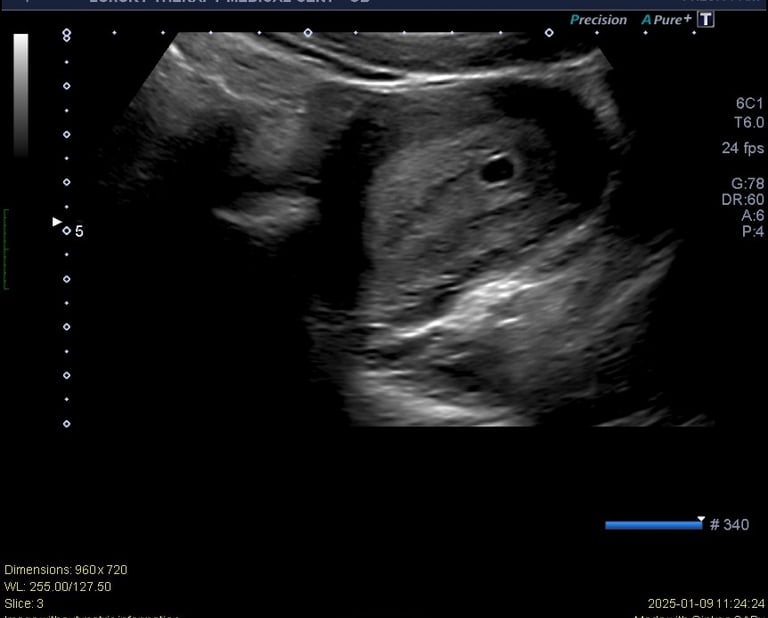

If you think you may be pregnant, the first step is confirming your pregnancy with a reliable ultrasound. At US Pregnancy in Hialeah, we provide fast and accurate pregnancy confirmation ultrasounds in a comfortable and professional environment.

Our experienced staff performs early pregnancy ultrasounds to confirm the presence of a gestational sac, estimate the gestational age, and help you begin your pregnancy journey with confidence.

A pregnancy confirmation ultrasound is an early ultrasound examination used to confirm that a pregnancy is present inside the uterus.

Early pregnancy ultrasounds are usually performed between 5 and 8 weeks of pregnancy for the most accurate confirmation.

A trained ultrasound technician performs the scan

Images of the uterus are obtained

The presence of an early pregnancy is evaluated

Gestational age may be estimated depending on development